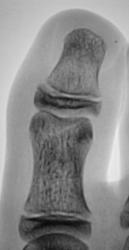

Травма. Пациент направлен врачом хирургом на рентгенографию переднего отдела стопы. Произведено исследование. Интерес у нас вызвал 1 палец. Какие мнения будут уважаемые коллеги?

Настолько качественная рентгенограмма, что передний край суставной поверхности дистального эпифиза средней фаланги первого пальца, который имеет форму буквы V, симулирует линию перелома...

это не перелом?

Я бы не исключила перелом, только не средней, а основной фаланги, средней то у первого пальца нет.